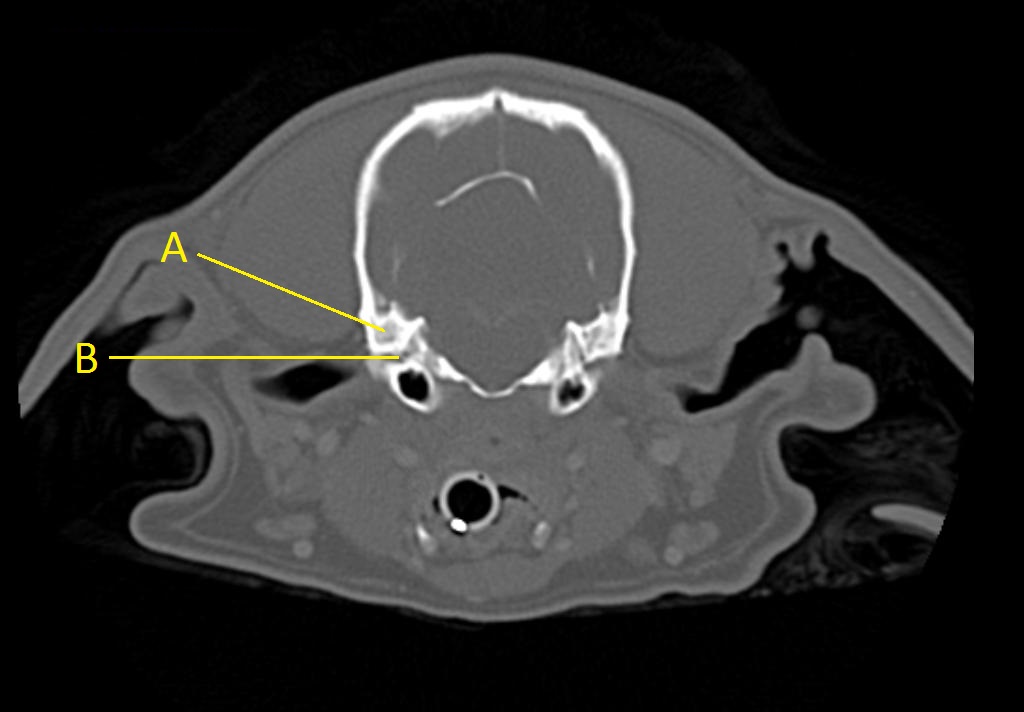

Q. Identify the structures labeled below:

A.

A. mastoid process

B. stylomastoid foramen